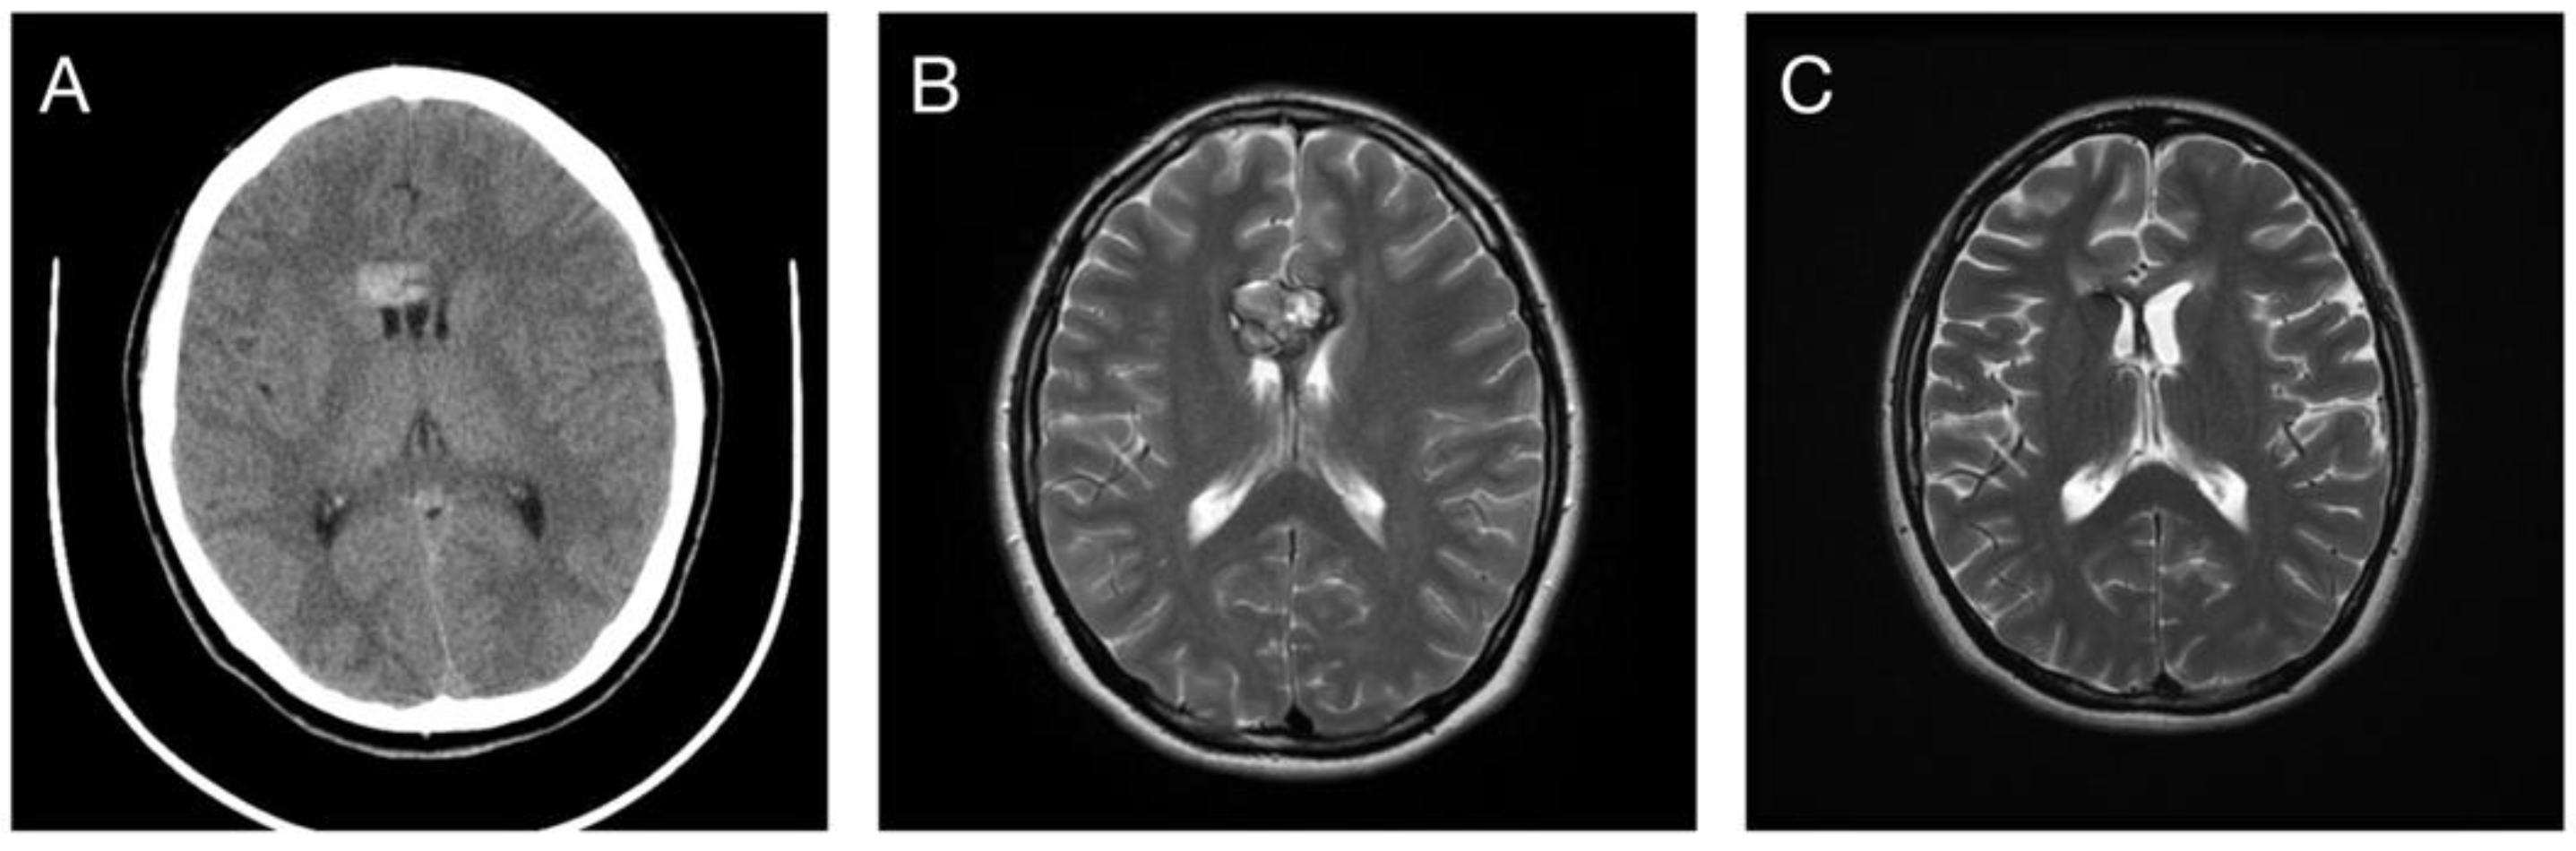

| Initial Zabramski classification | |

| Class I | 4 (13.3%) |

| Class II | 25 (83.3%) |

| Class III | 1 (3.3%) |

| Class IV | 0 (0%) |